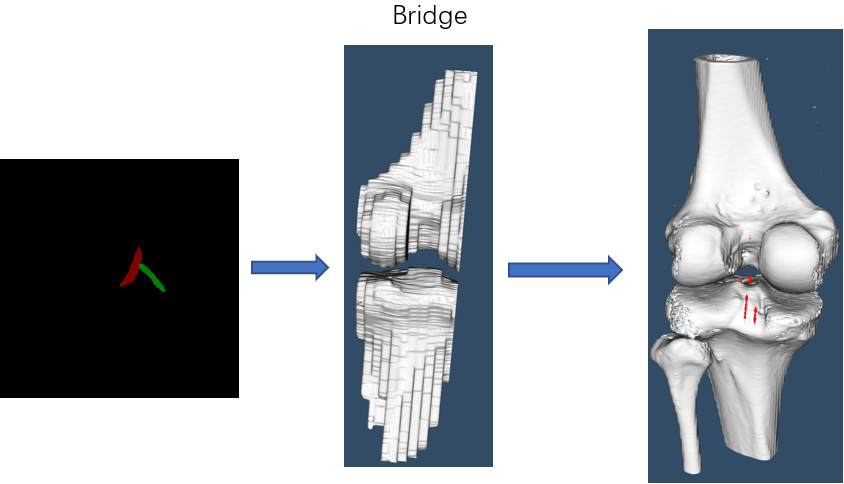

Cruciate ligament injury is very common in daily life. At present, many ligament reconstruction operations are based on the experience of doctors, and errors are inevitable. Extraction and reconstruction of cruciate ligament insertion is very important, which can help doctors to analyze and predict before surgery, and improve the success rate of surgery.